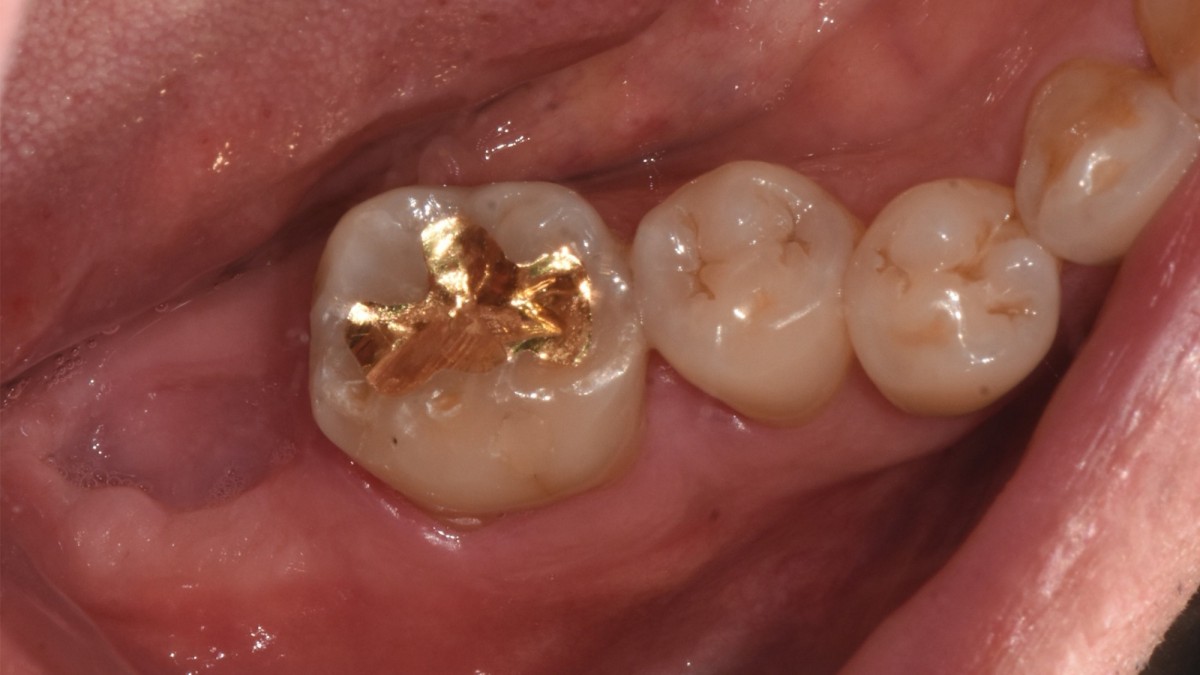

A 47-year-old male patient had a crown with an ill-fitting margin and crack-tooth syndrome in the lower 2nd molar. No systemic issue.